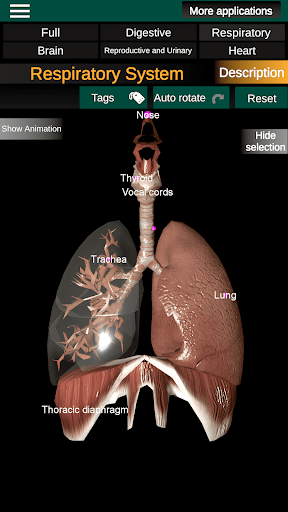

Internal Organs in 3D Anatomy لـ Vodafone Smart N9 Lite

(الأجهزة الداخلية في)

Internal Organs 3D Anatomy 3.4

يمكنك هنا تنزيل ملف حزمة تطبيق أندرويد "Internal Organs 3D Anatomy" الخاصة بجهازVodafone Smart N9 Lite مجانًا، نسخة ملف حزمة تطبيق أندرويد - 3.4 للتحميل على Vodafone Smart N9 Lite اضغط ببساطة على هذا الزر. إنه سهل وآمن. نحن نقدم فقط ملفات حزمة تطبيق أندرويد الأصلية. إذا انتهكت أية مواد موجودة في الموقع حقوقك قم بإبلاغنا من خلال